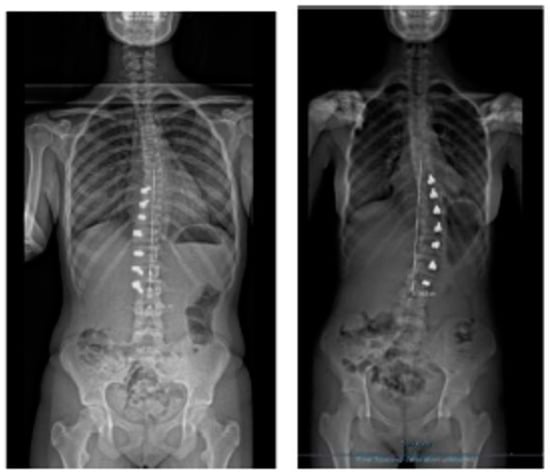

Correction of two (scoliosis and hypokyphosis) of the three plane deformities in scoliosis has already been explained, but how rotational correction happens in these growth-friendly procedures is not clear. We know that with the progression of scoliosis, the rotation of the vertebral bodies towards the concavity increases due to the imbalance/disturbance of the different growth plates and synchondrosis in the growing spine. Tethering, either anterior or posterior, on the convexity of the curvature locks this progressive abnormal rotation and may allow the opposite side to de-rotate the vertebrae gradually with growth, thereby improving the rotational deformity and the rib hump, as shown (Figure 2).

Figure 2.

Radiological regression of rib hump with decrease of the prominent ribs.